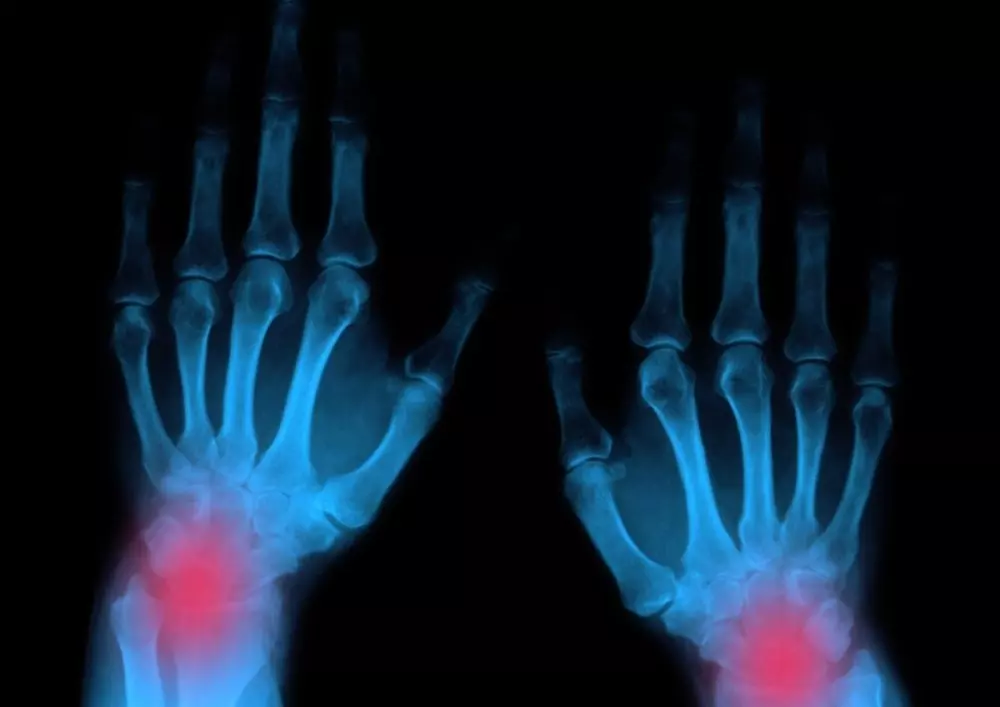

Reumatoidalne zapalenie stawów

„Reumatoidalne zapalenie stawów to przewlekła, zapalna, immunologicznie zależna choroba układowa tkanki łącznej. Charakteryzuje się nieswoistym, symetrycznym zapaleniem stawów, obecnością zmian pozastawowych oraz występowaniem licznych powikłań układowych prowadzących do niepełnosprawności, a w stadium zaawansowanym – do trwałego kalectwa” – pisze ekspert. Będą mogli zapoznać się Państwo z obrazem zmian stawowych i pozastawowych, a także diagnostyką i leczeniem w reumatoidalnym zapaleniu stawów. Choroba ta wymaga kompleksowego postępowania oraz szczegółowego planu leczenia, który w pełni odpowiada na potrzeby pacjenta i jest regularnie modyfikowany. Ponadto osoby cierpiące na reumatoidalne zapalenie stawów powinny korzystać z rehabilitacji, która opóźnia rozwój choroby i poprawia sprawność, a co za tym idzie samodzielność i umożliwia codzienne funkcjonowanie.